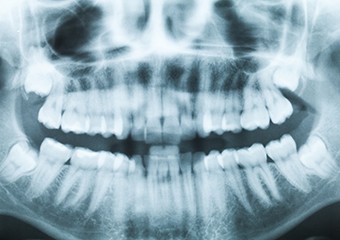

顎関節症とは、顎関節や周辺の筋肉が痛い、噛むときにカクカク音がする、口が開きづらいなどを主な症状とする慢性的な疾患です。通常、顎が動くときに「関節円板」と呼ばれる顎関節の一部が、上下の顎のクッションの役割を果たすことで、問題なく口を開けたり、食べ物を噛んだりすることができます。

しかし、この関節円板が何らかの原因でズレる、変形することでスムーズに顎が動かせなくなる状態が続き、顎関節症となります。なお、関節円板の障害だけでなく顎周辺の筋肉や靭帯へ大きな負担がかかったり、顎関節の骨自体が変形して、発症していることもあります。

一般的に顎関節症はさまざまな原因が重なって症状がでているものがほとんどで、原因を一つだけに絞るのが難しいとされております。そのため、まず思い当たる部分からアプローチし、治療をはじめていきます。